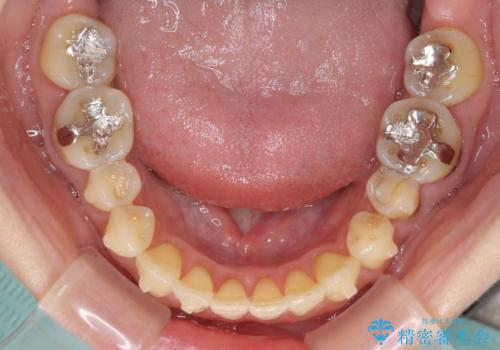

- 歯列不正と、どこで咬んで良いのか分からない咬み合わせを気にして来院された患者様です。

下顎骨は左側にシフトしており、咬み合ったときには奥歯と前歯の一部しか接触していない状態でした。

骨格的な左右差は歯列矯正は改善できないため、上下歯列が全体的に接触することをゴールとしてインビザラインにて矯正治療を行うこととしました。